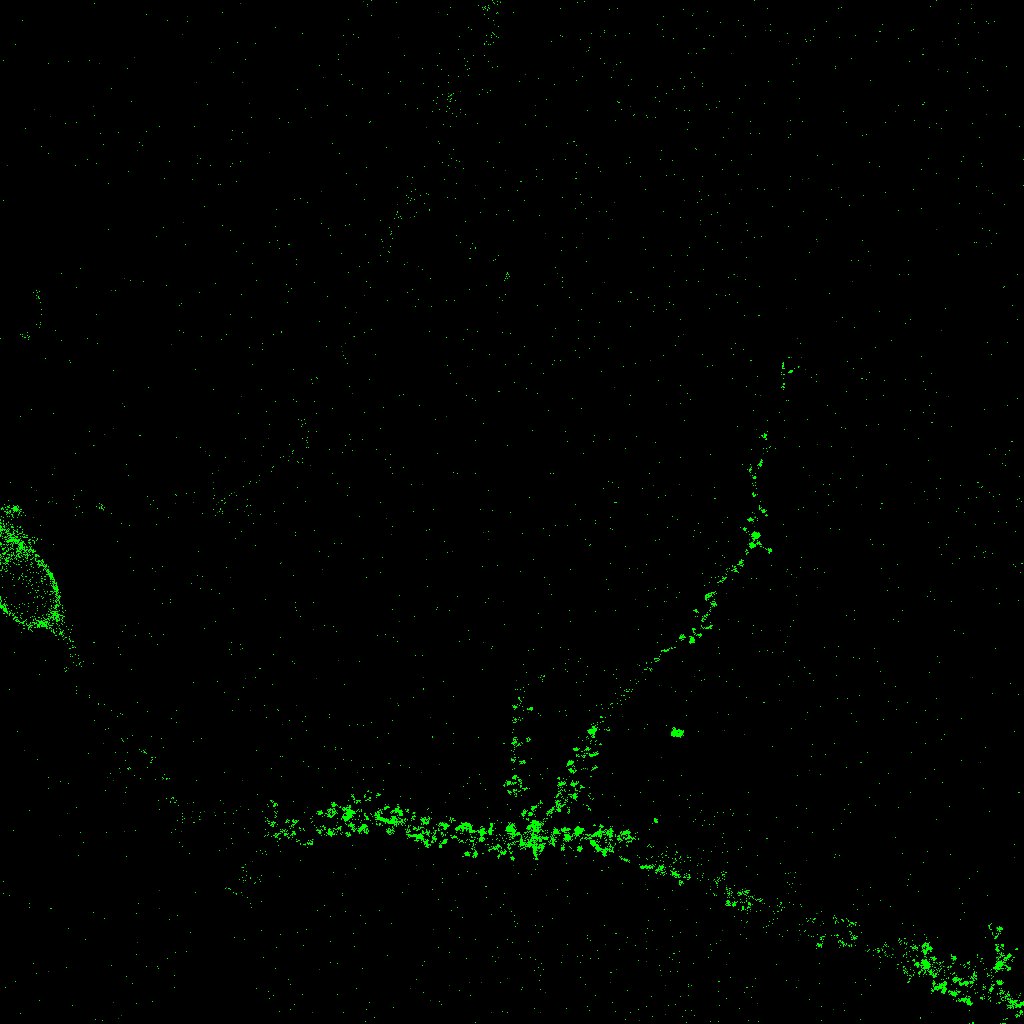

Para la automatización de los procesos llevados a cabo por el grupo PSE, se planteó en primer lugar el problema del cálculo del número de sinapsis, que son los puntos de conexión entre las neuronas. Las sinapsis tienen una gran importancia en el campo de investigación tratado ya que están relacionadas con las capacidades de cálculo del cerebro, y la posibilidad de incrementar el número de contactos sinápticos puede ser una ventaja importante en el tratamiento de enfermedades neurodegenerativas. Para realizar el recuento de sinapsis se necesitan dos imágenes diferentes de la misma neurona que se obtienen usando técnicas de laboratorio, más concretamente utilizando dos marcadores que reconocen estructuras sinápticas; esas dos imágenes se superponen y se realiza el recuento de las sinapsis. En la figura 1, de tamaño 1024×1024102410241024\times 1024 píxeles, o equivalentemente 228×228228228228\times 228 micras, las sinapsis son los puntos que aparecen en blanco.

Refer to caption

Figura 1: Recuento de sinapsis

Uno de los conceptos más importantes para nuestro trabajo es la noción de conexión, o más concretamente, el cálculo del número de componentes conexas. Ésta es la idea fundamental empleada para el recuento de sinapsis en una imagen de cultivo: tras solapar dos imágenes diferentes de la misma neurona en un mismo instante obtenidas tras la aplicación de dos marcadores primarios y señalar manualmente la región en la que debe realizarse la medida, las distintas sinapsis corresponden a las componentes conexas obtenidas en la intersección. El programa realiza este cálculo, marca sobre la imagen las distintas apariciones y nos da el número total de sinapsis (componentes conexas) localizadas.

El primer plugin que desarrollamos se denomina SynapCountJ [13], y se utiliza para calcular el número de sinapsis que aparecen en la imagen de una neurona. Como ya se ha comentado anteriormente, el programa recibe dos imágenes diferentes de la misma neurona tomadas en un momento concreto tras la aplicación de dos marcadores, en rojo y verde. El usuario debe señalar manualmente la región en la que va a realizarse la medida, esto es, las distintas ramas (dendritas) de la neurona, lo que nos da una tercera imagen en azul (para esta parte hacemos uso del plugin NeuronJ [17]). Con estos datos, el programa marcará como sinapsis los puntos de rojo, verde y azul que coincidan en las tres imágenes (y que aparecerán como puntos blancos, véase la figura 1). El usuario puede modificar los parámetros introduciendo el rango tanto de rojo como de verde que considera que debe poseer una sinapsis. Según se va eligiendo el rango se pueden ir observando la zonas de la neurona que se van a marcar como sinapsis para hacer una mejor estimación. Finalmente, el programa presenta la imagen con las sinapsis señaladas y muestra también una tabla en la que se indican el número de sinapsis y la densidad obtenida. Véanse las dos imágenes de partida y el resultado dado por SynapCountJ (las tres en escala de grises) en la figura 8. En esta imagen las sinapsis corresponden a los puntos más oscuros dentro de la zona señalada.

Refer to captionRefer to captionRefer to caption

Figura 8: Resultado de SynapCountJ

Por ejemplo, para validar el plugin SynapCountJ se realizó un estudio comparativo en el que se analizaron 13 fotografías individuales a neuronas de cultivos de 12 días (es decir, en el laboratorio se preparó una muestra de neuronas dejando pasar 12 días antes de ser estudiada). En los experimentos biológicos se suelen estudiar dos muestras: una en la que se ha aplicado la sustancia a estudiar (lo que se denomina abreviadamente “tratamiento”) y otra en la que las medidas se realizan en el medio natural sin haber intervenido de ningún modo (“control”). De esta manera se puede saber si el tratamiento aplicado tiene algún efecto sobre la muestra. En el caso que nos ocupa, se trata de saber si el tratamiento tiene un efecto potenciador o inhibidor de la densidad sináptica. En la figura 12 se puede observar que al realizar la identificación y el recuento de manera manual se obtiene una media de 24.12 sinapsis en el control (PTD4 5μg/ml5𝜇𝑔𝑚𝑙5\mu g/ml) y 16.74 sinapsis en el tratamiento (SB 415286 10μM10𝜇𝑀10\mu M). Así mismo los resultados obtenidos mediante el plugin son similares: se localizaron 26.03 sinapsis de media en el control y 16.50 sinapsis en el tratamiento. A pesar de las diferencias en el recuento, el porcentaje de inhibición medido con ambos procedimientos es el mismo, un 30,6%percent30.630{,}6\leavevmode\,\%{} de manera manual y un 36%percent3636\leavevmode\,\%{} de modo automático. Hay que señalar que en este caso la densidad sináptica disminuye en el tratamiento frente al control debido a que el estudio se ha realizado en cultivos de 12 días. Se ha constatado que para este tiempo de cultivo, el tratamiento tiene un efecto inhibidor de la densidad sináptica. Sin embargo en cultivos de 21 días el estudio muestra que la densidad sináptica puede aumentar aproximadamente un 60%percent6060\leavevmode\,\%{}, teniendo un efecto potenciador (véase [16]).

Refer to captionRefer to caption

Figura 12: Datos de validación del plugin SynapCountJ